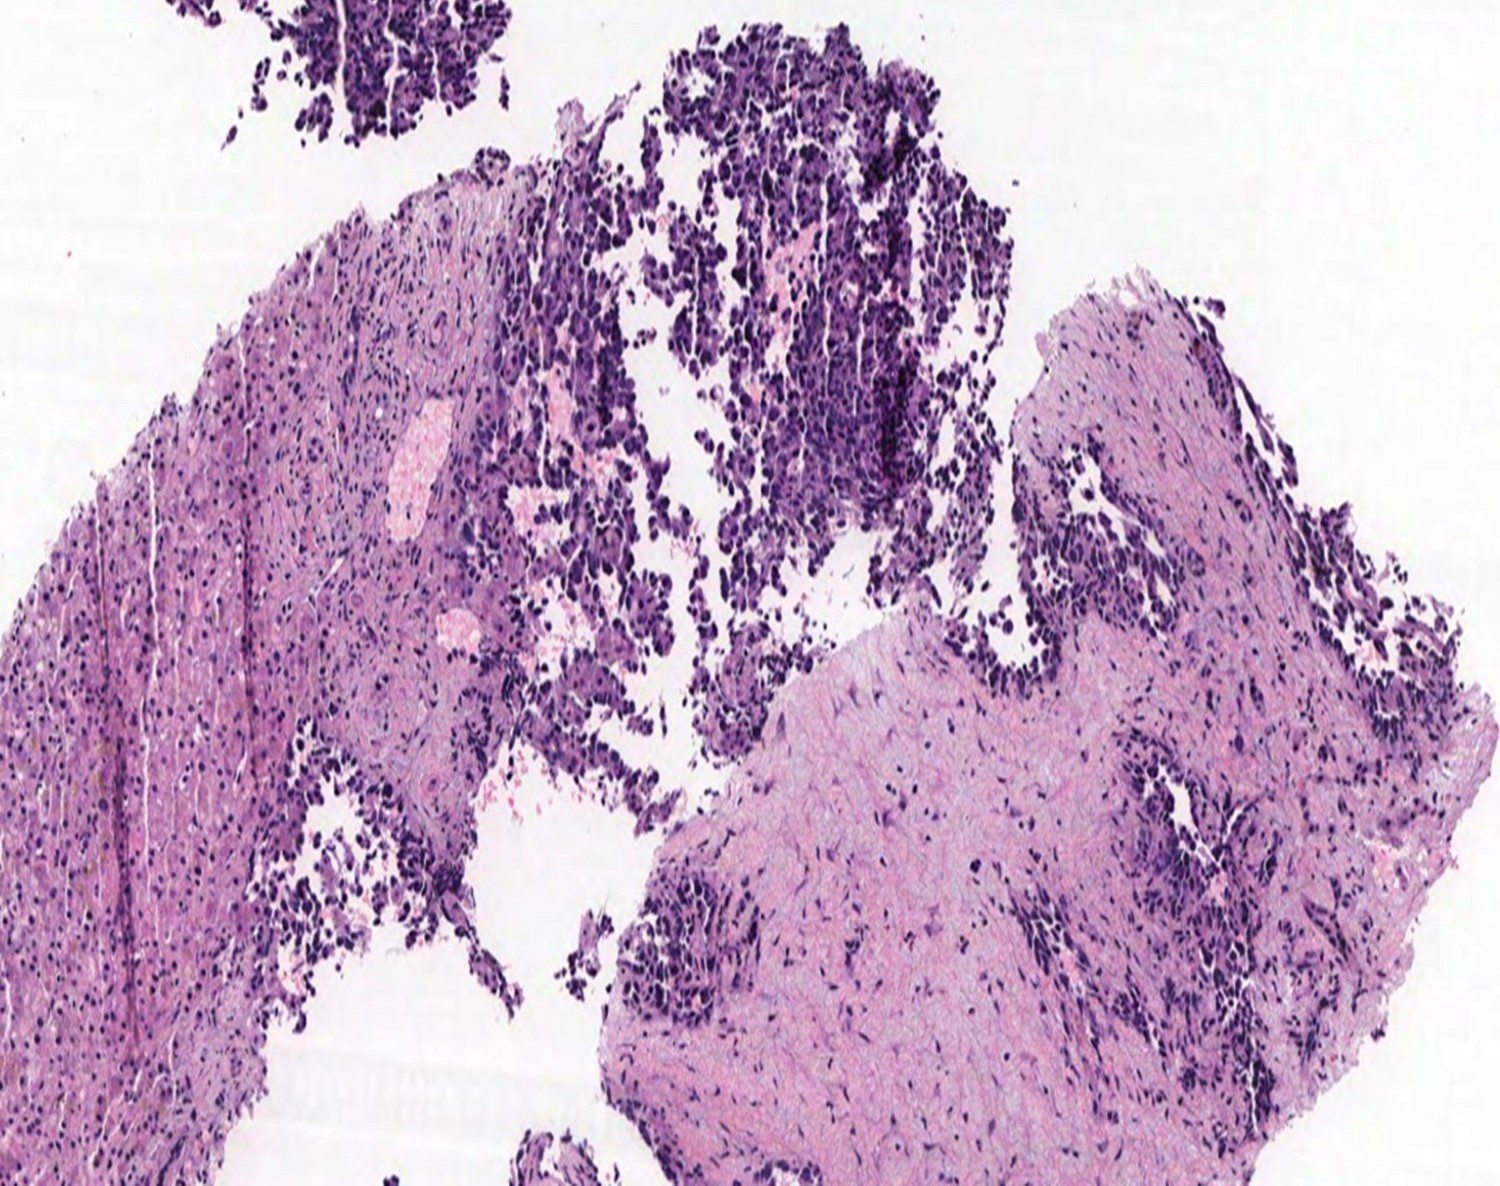

Microscopic (histologic) description

- 2 main histologic growth patterns were described (Am J Surg Pathol 2019;43:581)

- Non-mass forming

- Sinusoidal

- Dilated sinusoids lined by atypical endothelial cells seen in angiosarcoma with hyperchromatic nuclei

- Peliotic

- Blood pools and fibrin surrounded by hepatocytes

- Peripheral clusters of atypical endothelial cells seen in angiosarcoma mixed with inflammatory cells may extend into the sinusoids

- Mass forming

- Vasoformative shows architectural complexity and interconnecting vascular channels

- Anastomosing vessels and haphazard vascular channels

- Endothelial cells show tufting, atypia and mitotic figures

- Nonvasoformative shows epithelioid to spindled morphology

- Epithelioid morphology (epithelioid angiosarcoma) is most common (Am J Surg Pathol 2004;28:298)

- Solid nests or sheets of tumor cells

- Tumor often invades into sinusoids and hepatic venules at the periphery

- Cells have eosinophilic cytoplasm and oval nuclei

- Chromatin can be vesicular

- Multinucleated giant cells can be present

- Unusual growth patterns (Am J Surg Pathol 2019;43:581)

- Whorls of spindle cells in a background of chronic inflammation and loose myxoid to sclerotic stroma